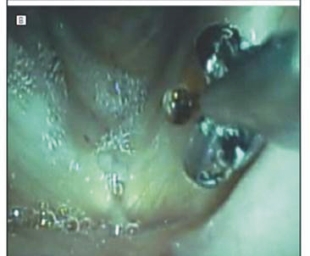

圖一、綠光雷射擊發,可選擇性凝固聲帶息肉周圍之細小血管

圖二、從內視鏡中伸出特製之切片鉗,可直接夾除息肉